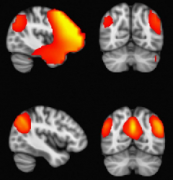

局灶性MRI異常增加了術(shù)前擬手術(shù) 治療癲癇患者 的致癇區(qū)成功勾畫的機(jī)會(huì)(Duncan和Sagar, 1987;Fish等人,1993年;斯賓塞,1995;艾蒙等,1996;Cascino, 2004;Tonini等人,20...